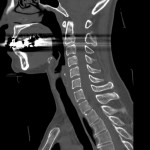

CT検査

当院では各診療科からの検査依頼があり、診断用CTが2台、放射線治療計画用CTが1台稼動しています。

CTの寝台に寝ていただき、その寝台が動きながら検査を行います。寝台がガントリー(X線発生器と検出器等から構成)と呼ばれるドーナツ状の機械を通過する際に、X線を照射し、検出しています。物質のX線の吸収差を利用して、360度方向からのデータを再構成することで輪切りの画像が完成します。空気や水などX線を吸収しにくいものは黒く、骨などX線を吸収しやすいものは白く表示されます。

当院のCT装置の最薄スライス厚は0.625mmで、これにより一つの断面だけでなくいろいろな角度からの断面を構築することや、血管や骨の3次元表示を可能にしています。また、2021年2月に導入された装置では、2種類のエネルギーを使用して撮影することで、コントラストの増強、アーチファクトの低減、さらに特定の物質を強調したり抑制した画像が作成でき、診断能の向上が見込めます。

脊髄腔造影

腰から脊髄腔に造影剤を注入しヘルニアなどを調べます。

また透視室での検査の後でCTを撮影し、より細かく検査をします。